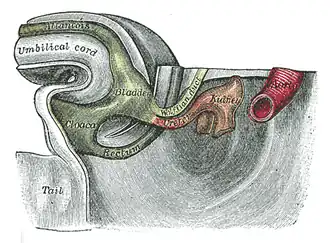

Os ureteres se desenvolvem a partir dos botões uretéricos, que são bolsas externas do ducto mesonéfrico. Este é um ducto, derivado do mesoderma, encontrado no embrião inicial.[8] Com o tempo, os botões se alongam, movendo-se para o tecido mesodérmico circundante, dilatam-se e dividem-se em ureteres esquerdo e direito. Eventualmente, sucessivas divisões desses botões formam não apenas os ureteres, mas também a pelve, cálices maiores e menores e dutos coletores dos rins.[8]

O ducto mesonéfrico está conectado à cloaca, que ao longo do desenvolvimento se divide em um seio urogenital e o canal anorretal.[8] A bexiga urinária se forma a partir do seio urogenital. Com o tempo, conforme a bexiga aumenta, ela absorve as partes vizinhas dos ureteres primitivos.[8] Finalmente, os pontos de entrada dos ureteres na bexiga se movem para cima, devido à migração ascendente dos rins no embrião em desenvolvimento.[8]